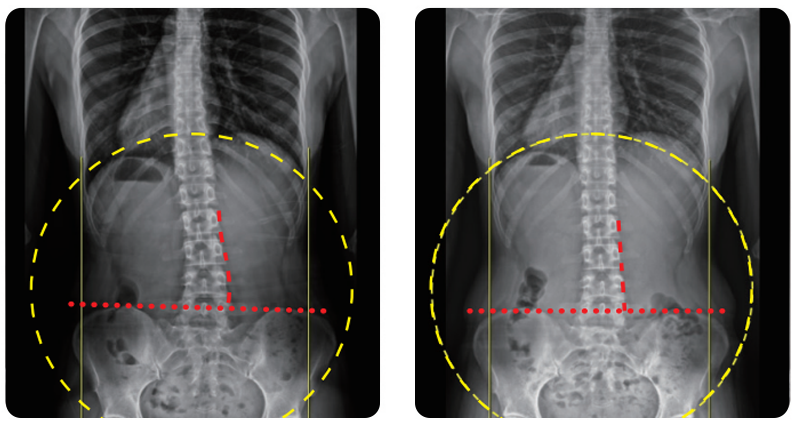

Before & After

척추측만증 교정 사례

• Case 01 30대 / 직장인 / 치료기간 : 3개월

• Case 02 10대 / 학생 / 치료기간 : 1.5개월